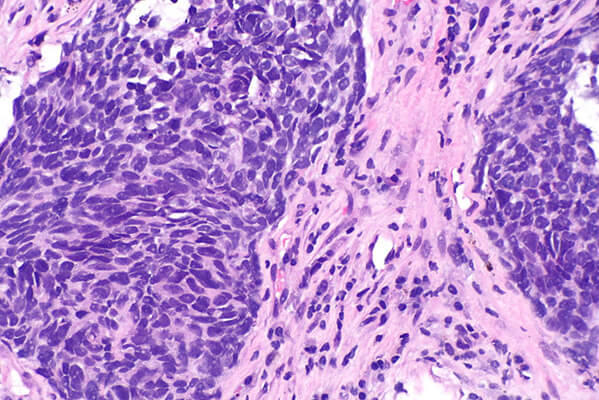

A micrograph showing a nonsquamous non-small cell lung cancer.

On May 10, the drug was approved to be used with pemetrexed (Alimta®) and carboplatin for patients with previously untreated advanced nonsquamous NSCLC, regardless of whether their tumors express the protein PD-L1.